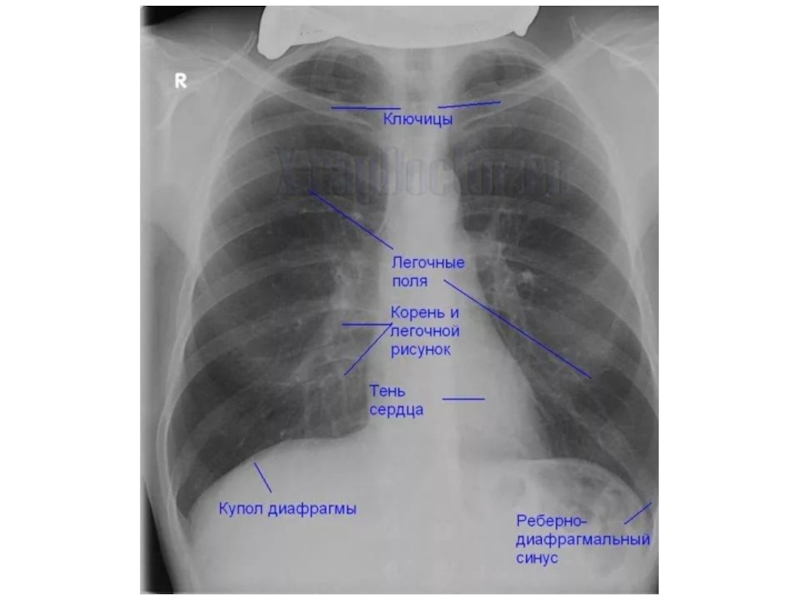

Рентгенологические признаки пневмонии – рентгенография является наиважнейшим и

незаменимым методом исследования для подтверждения клинического диагноза пневмонии.

При подозрении на пневмонию рентгенография грудной клетки выполняется в двух проекциях: прямой и боковой проекциях. Типичным рентгенологическим признаком пневмонии является затемнение легочной ткани, которое может быть очаговым, сливным, сегментарным (полисегментарным), долевым или еще более распространенным (тотальным). Изменения на рентгенограмме (распространенность инфильтрации, наличие или отсутствие плеврального выпота, полостей деструкции) указывают на тяжесть заболевания, помогают в выборе антибактериальной, симптоматической и другой (например, плевральная пункция) терапии.

Рентгенография органов грудной клетки. Рентгенологически характерным для крупозной пневмонии является гомогенное затемнение той или иной доли, или ее сегментов. При очаговой пневмонии у большинства больных выявляются очаговые тени средней или малой интенсивности, часто с неровными контурами.